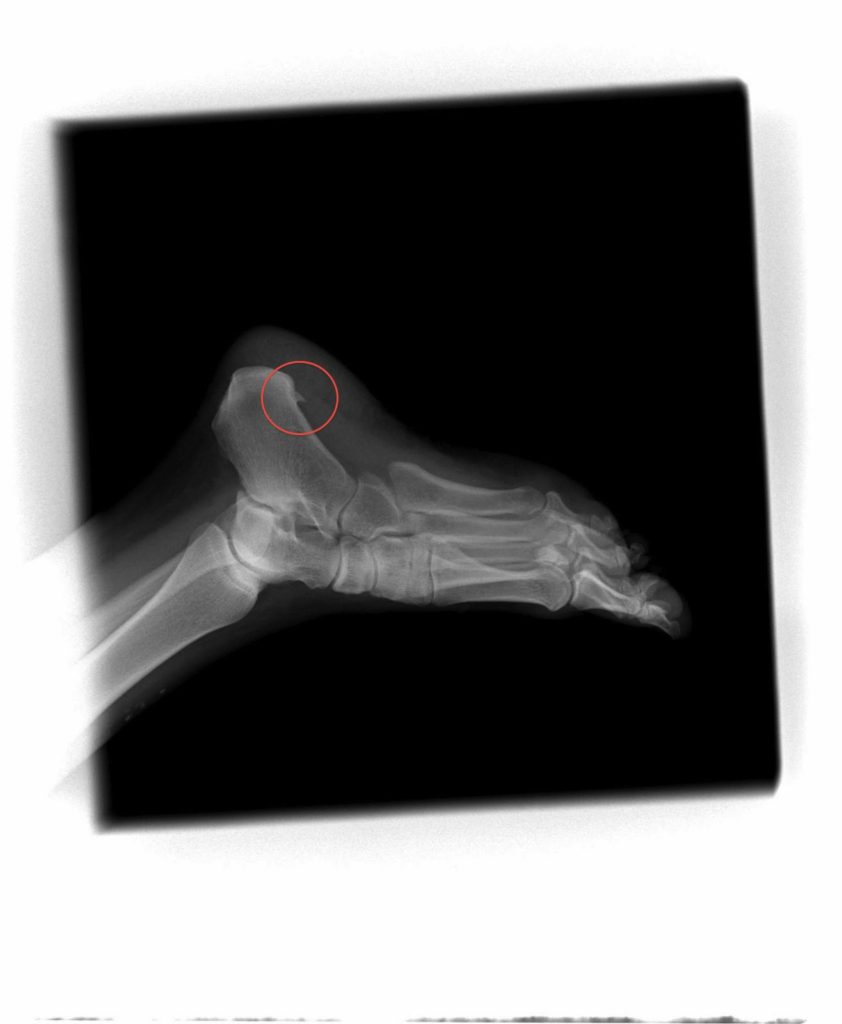

Heel Spur. No Kidding.

Most of you know I love walking and hiking. Weather permitting (yes, fair weather hiker) I love to go